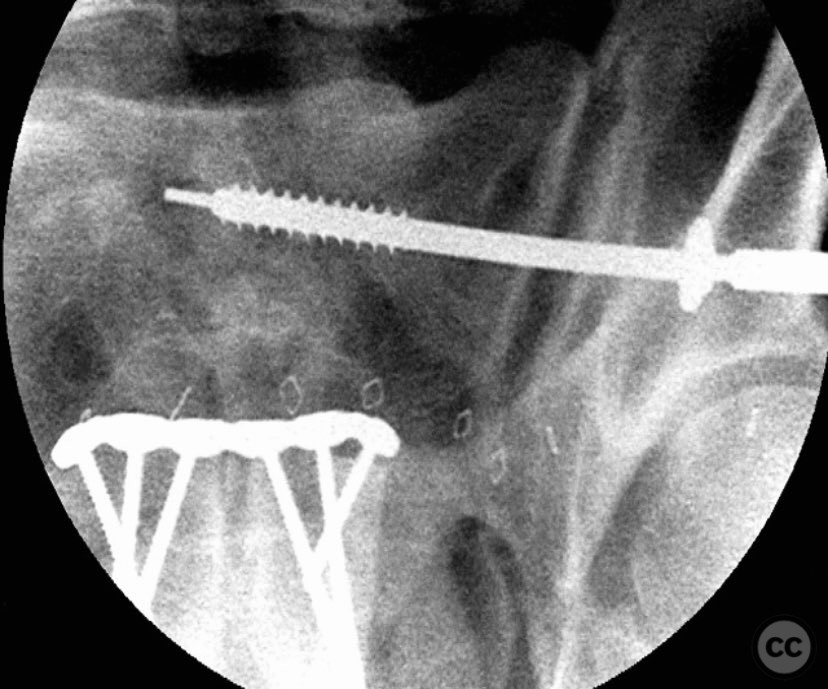

Anatomical surgical approach:  A lower midline infraumbilical incision was made to expose the symphysis pubis. Subperiosteal dissection was performed to mobilize the rectus abdominis insertions and expose the pubic bodies. A pelvic reduction clamp was applied with tines docked in dense bone or soft tissue as dictated by local tissue quality, oriented to correct deformity while avoiding interference with planned plate placement. Following reduction, a contoured anterior symphyseal plate was applied and secured with cortical screws. Upon removal of the clamp, persistent SI joint malreduction was noted. Under fluoroscopic guidance, a percutaneous pathway was prepared for a cannulated iliosacral lag screw, traversing the posterior ilium into the upper sacral segment, ensuring safe passage relative to neurovascular structures.

The intraoperative course revealed that indirect reduction of the incomplete SI joint injury via anterior stabilization was insufficient, necessitating direct percutaneous fixation. A single cannulated iliosacral oblique lag screw was inserted under fluoroscopic control, achieving reduction, compression, and stabilization of the SI joint. Surgeon-specific technical consideration included avoidance of large-diameter drills for the posterior ilium due to limited bone stock (approximately 3 cm of ilium available for purchase), and the preference for an appropriately sized washer to optimize compression without risking iatrogenic fracture.

Orthopaedic implants used:   3.5 mm anterior symphyseal plate with cortical screws; 7.0 mm cannulated iliosacral lag screw with washer